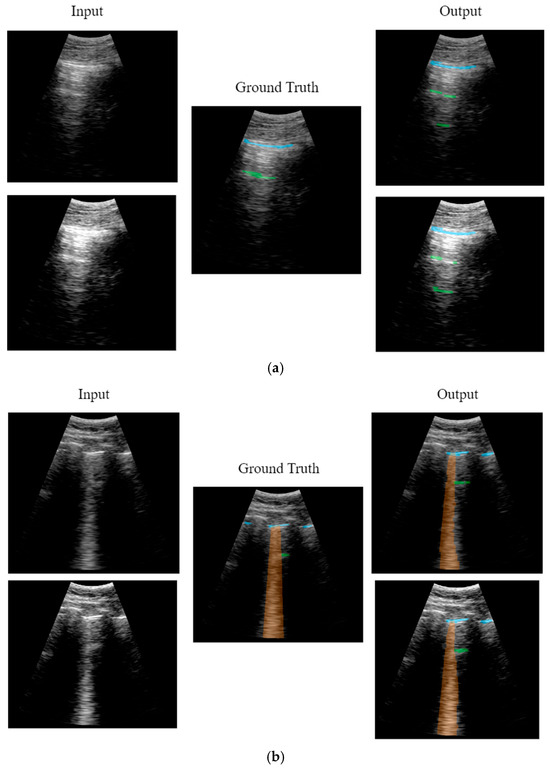

CNN Output

Model Prediction